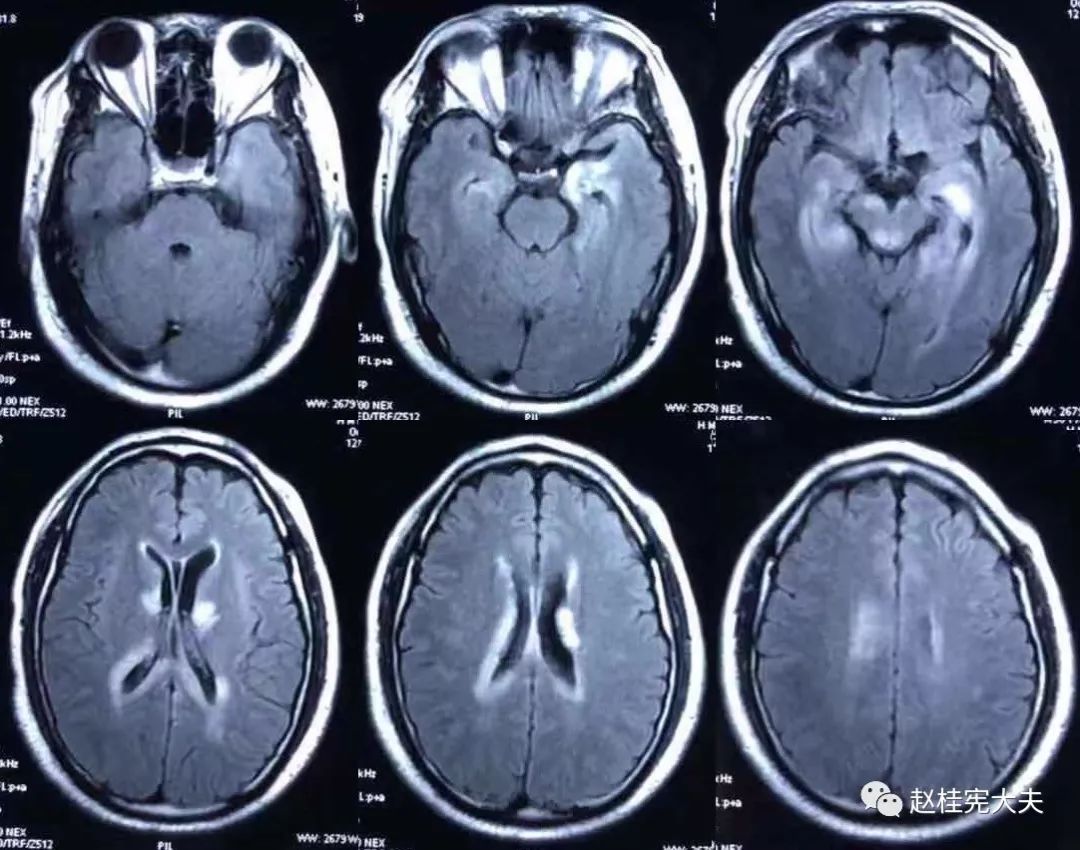

2018.7.6头颅MRI:胼胝体、穹隆及双侧脑室旁、基底节区、右侧延髓、桥臂异常信号,脱髓鞘病变考虑。头颅MRS:左枕叶病变区MRS显示:NAA下降,Cho升高,Cho/NAA=3.86,并见倒置乳酸峰。

2018.7.10磁共振增强:脑室周边病灶轻度强化。

2018.10复查头颅MRI:胼胝体压部、左侧部分枕颞叶、侧脑室枕角旁、中脑脱髓鞘病变,视神经脊髓炎谱系病?结合对照前片(7.4)病变范围有所缩小。

我看到患者时的思考:当了解了患者前期诊疗经过后,在看到患者磁共振片子时,我的第一反应就是淋巴瘤。尽管患者激素治疗后症状有好转,病灶在磁共振上看起来也是有好转,但淋巴瘤也会出现这样的表现。

我对满脑室边的病灶的体会是:遇到这样的病例,首先要考虑感染、肿瘤(如室管膜瘤、生殖细胞瘤、淋巴瘤或转移瘤脑室播散等等),炎症要放到后面去考虑,脱髓鞘的诊断要打个大大大大的?。炎症中,血管炎不像,自免脑也不是很支持,尽管边缘系统似乎也有受累,但患者边缘叶脑炎的精神、行为异常、癫痫等症状很少,而且磁共振上看去除了边缘系统,整个脑室系统都有受累,这个和常见自免脑不符。视神经脊髓炎谱系病?尽管病灶在水通道蛋白富集区,但这样的视神经脊髓炎(视神经和脊髓均未受累,近脑室边的异常信号)至少罕见,即使诊断,也应该是排除其它的疾病后才可能考虑。

患者住院期间还请眼科会诊,除双眼玻璃体轻度浑浊,视力、视野、OCT均未见明显异常,未建议行玻切明确诊断。患者入院后嗜睡症状有加中,但一直未诉头痛,仅是头昏,静滴甘露醇症状减轻不明显。复查头颅磁共振平扫+增强:病灶范围较前明显扩大。轻度强化。